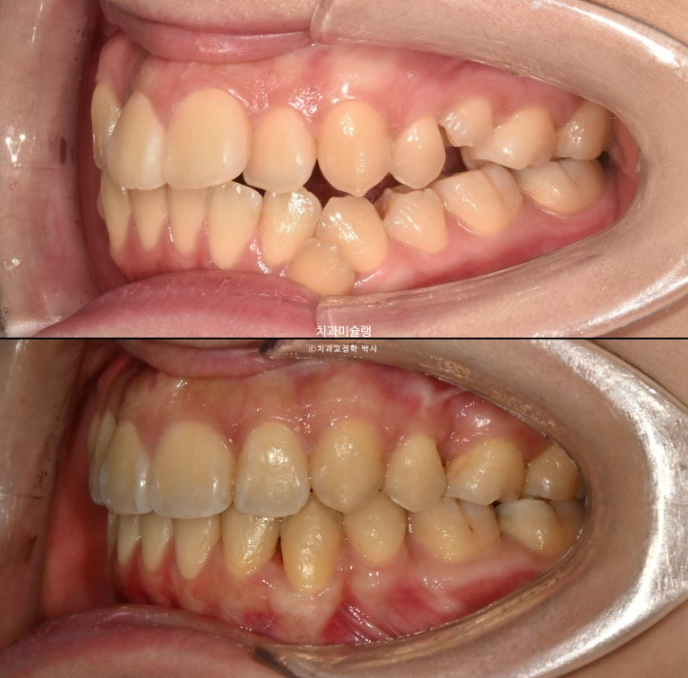

23.10~26.01

교합이 좋습니다.

스마일라인은 아랫입술과 평행하여 조화롭습니다.